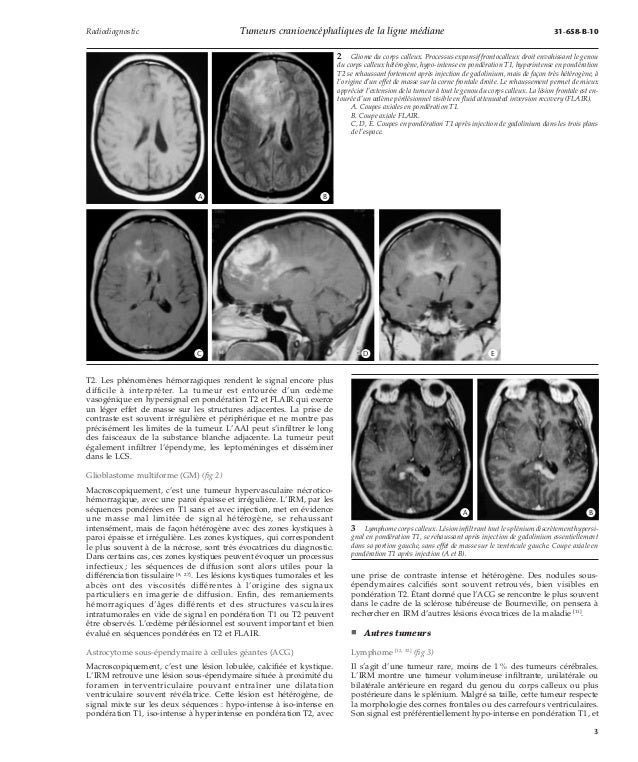

Tumeurs Cranioencephaliques De La Ligne Mediane